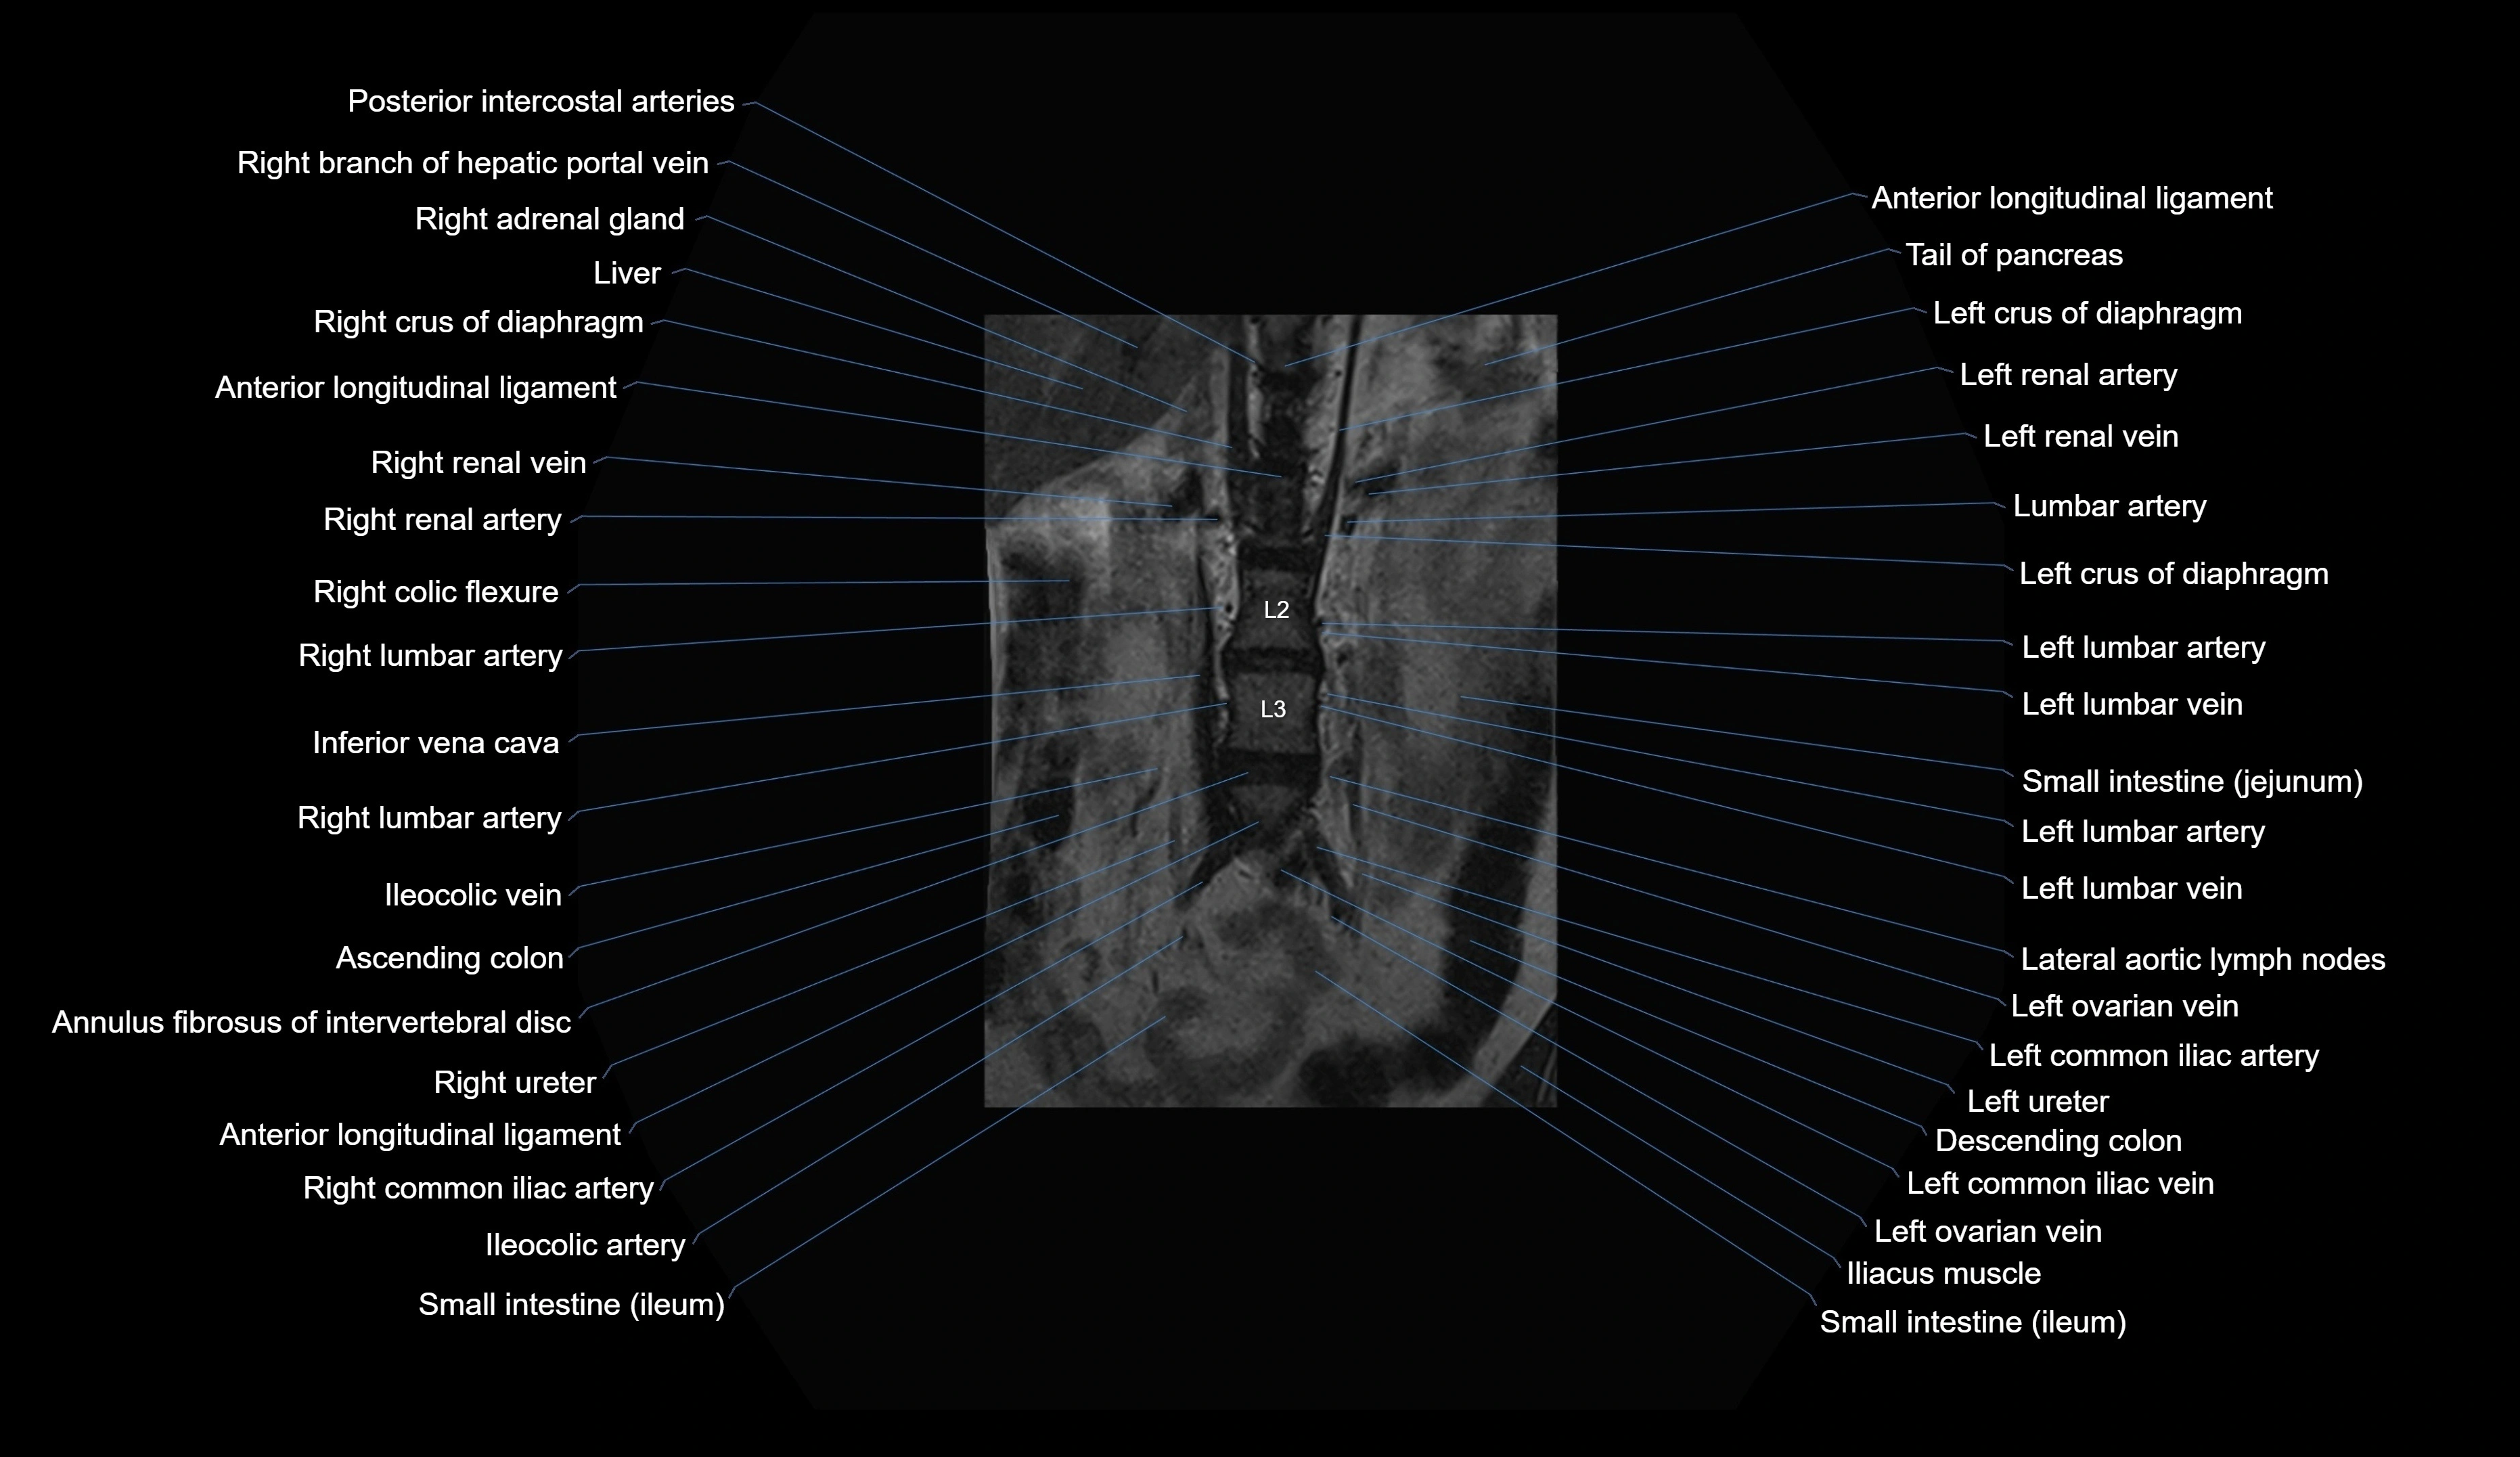

MRI images